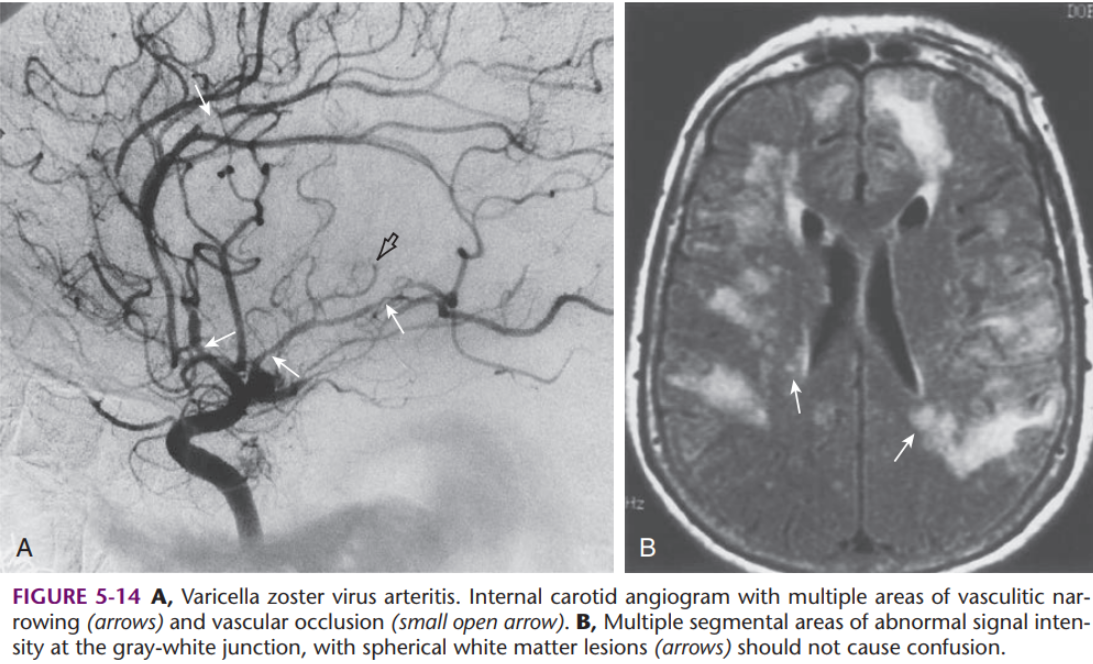

Encéphalite Varicelleuse (VZV)

- Réactivation de varicelle latente dans le ganglion dorsal / nerf cranien → Zona

- Chez les immunosupprimés (HIV) ++

- Fait des vasculites des artères intra-cranienens